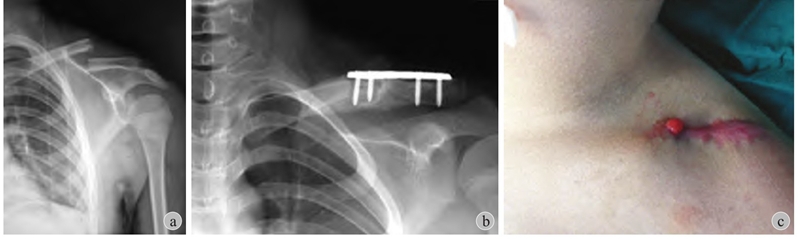

(1) 一般来说小年龄患儿的干部骨折不需要切开复位内固定,以股骨干为例,4 岁之前通常不用内固定治疗,4~10 岁之间通常选用弹性针固定,11 岁以上一般考虑青少年锁定髓内钉 (图3)。(2) 锁骨骨折儿童期通常不需要切开复位内固定 (图4)。在面对家长强烈的手术意愿下,应该与家长沟通选择合适的治疗方式,坚守儿童骨折的治疗原则。倘若因违背手术适应证而造成术后骨不连、骨髓炎等严重并发症,不仅患者的利益受到损害,更可能会引起诉讼纠纷。

图4 患儿 男 10岁

a:左锁骨骨折应考虑保守治疗;b:外院行切开复位+接骨板固定;c:术后发生感染及骨髓炎